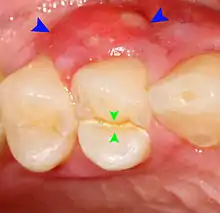

- Decay (green) with apical abscess (blue)